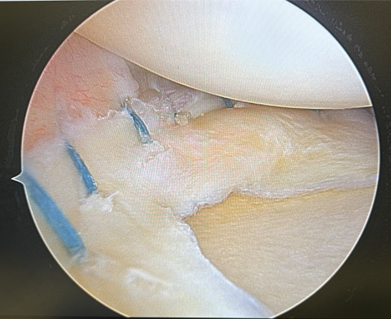

There are a few ways to help fix the meniscus to get your knee on the path to start feeling better and prevent the faster wear and tear to your knee. The way we fix the tear depends on the type and location of the tear. If the tear is able to be repaired, then we use stitches inside the knee to sew the tear back together. This will allow the meniscus to heal and restore its normal shape. Figure 1 shows a bucket handle tear of the meniscus. In this case, we opted to repair the meniscus (Figure 2) to restore knee biomechanics. If the tear is not able to be sewn back together, then we trim the edges and smooth out the meniscus similar to trimming a hangnail on your finger.

Figure 2